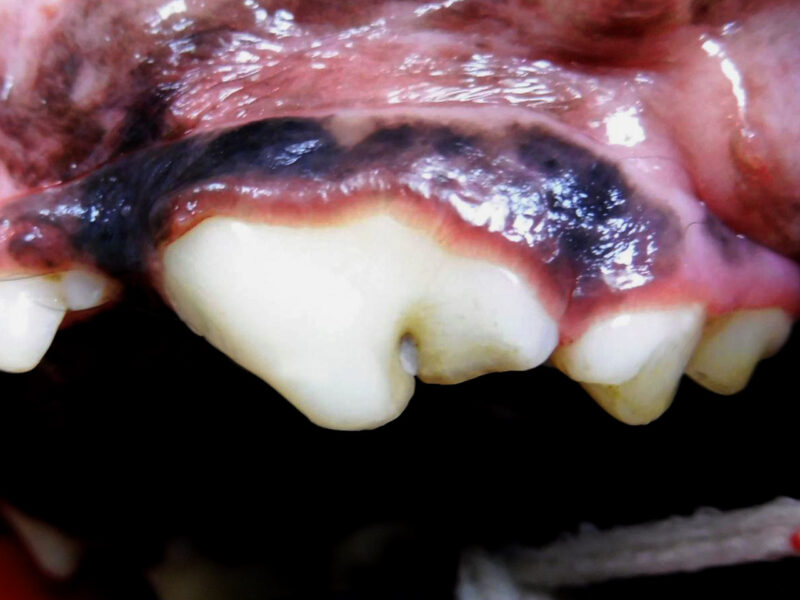

Zwei Wochen später ist es soweit: Mia wird zur Zahnstatuserhebung und Versorgung der Zahnfraktur in der Tierklinik vorgestellt. Nachdem sie in Frauchens Armen friedlich einschläft geht es in den Zahn-OP. Zuerst werden die Zähne mittels Ultraschall von Zahnstein und Plaque befreit. Im Anschluss werden - wie auch bei uns beim Zahnarzt - alle Zähne sondiert und geröntgt. Fast 30% aller klinisch wichtigen Befunde sind bei Hunden nur auf Dentalröntgen zu erkennen; bei der Katze sind es sogar noch mehr. Nur so kann der Tierarzt die Narkose ausreichend nutzen um alle für das Tier schmerzhaften Probleme zu behandeln.

Bei Mia gibt es außer der bekannten Zahnfraktur des linken Oberkieferreißzahns (Prämolarer 4) keine Auffälligkeiten. Bei der Sondierung und Betrachtung der Bruchkante mit der Lupenbrille zeigt sich, dass noch eine ganz feine Schicht Zahnsubstanz (Dentin) Mias Wurzelkanal bedeckt. Das Dentin bietet zwar noch einen gewissen Schutz, im Gegensatz zum Zahnschmelz (der beim gesunden Zahn die äußerste Schicht der Zahnkrone bildet) hat es jedoch feine Kanälchen durch die Bakterien eindringen könnten. Im Röntgenbild zeigt sich bisher kein Hinweis für eine bestehende Infektion, und zusammen mit der Besitzerin wird entschieden, dass Mia den Zahn erstmal behalten darf, aber in sechs Monaten erneut zur Zahnröntgenkontrolle kommen muss. Da die feine Dentinschicht über dem Wurzelkanal weder vor Infektionen noch vor Umwelteinflüssen schützt, wird die Bruchkante mit dem Bohrer geglättet und der Zahn mit Kunststoff versiegelt.